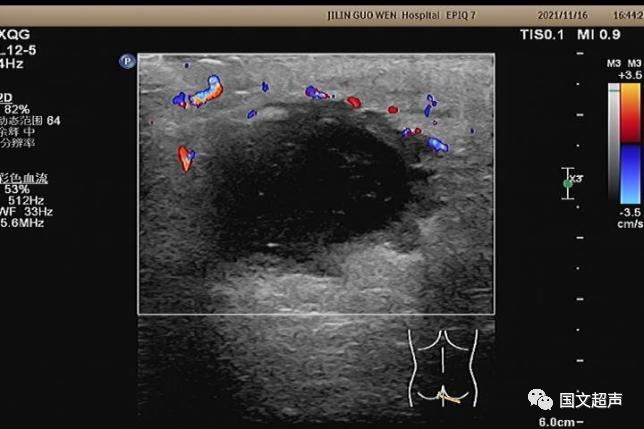

超聲檢查所見(jiàn):

肛周:7點(diǎn)鐘方向皮下脂肪層內(nèi)探及不均質(zhì)低無(wú)回聲包塊,范圍約4.6*3.0cm,較淺處距體表約0.6cm,邊界不清,周圍軟組織回聲增強(qiáng),CDFI:周邊血流信號(hào)豐富,輕加壓探頭有涌動(dòng)感,如下圖: